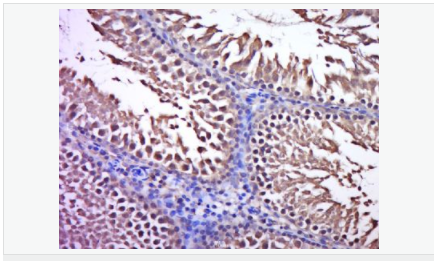

產品介紹C3orf32 (chromosome 3 open reading frame 32), also known as fls485, is a 353 amino acid protein encoded by a gene that maps to human chromosome 3p26.1. Chromosome 3 is made up of approximately 214 million bases encoding over 1,100 genes. Notably, there is a chemokine receptor gene cluster and a variety of human cancer related loci on chromosome 3. Particular regions of the chromosome 3 short arm are deleted in many types of cancer cells. Key tumor suppressing genes on chromosome 3 encode apoptosis mediator RASSF1, cell migration regulator HYAL1 and angiogenesis suppressor SEMA3B. Marfan Syndrome, porphyria, von Hippel-Lindau syndrome, osteogenesis imperfecta and Charcot-Marie-Tooth disease are a few of the numerous genetic diseases associated with chromosome 3.

Tissue Specificity:

Expressed in enterocytes of small and large intestinal mucosa (at protein level). Expressed in enterocytes, chromaffine and interstitial cells.